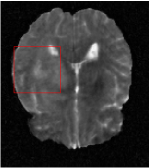

All the experiments are implemented on a Windows workstation with Intel Core i9 CPU at 3.3GHz and an Nvidia GTX-1080Ti GPU with 11GB of graphics card memory via TensorFlow Abadi et al. (2016). The parameters in the proposed network are initialized by using Xavier initialization Glorot and Bengio (2010). We trained the meta-learning network with four tasks synergistically associated with four different CS ratios: 10%, 20%, 30%, and 40%, and test the well-trained model on the testing dataset with the same masks of these four ratios. We have 300 training data for each CS ratio, which amount to total of 1200 images in the training dataset. The results for and MR reconstructions are shown in Tables 5.4 and 5.4 respectively. The associated reconstructed images are displayed in Figures 1 and 3. We also test the well-trained meta-learning model on unseen tasks with radio masks for skewed ratios: 15%, 25%, 35%, and random Cartesian masks with ratios 10%, 20%, 30% and 40%. The task-specific parameter for the unseen tasks are retrained for different masks with different sampling ratios individually with fixed task-invariant parameters . In this experiments, we only need to learn for three skewed CS ratios with radio mask and four regular CS ratios with Cartesian masks. The experimental training proceed on less data and iterations, where we performed on 100 MR images with 50 epochs. For example, for reconstructing MR images with CS ratio 15% radio mask, we fix the parameter and retrain the task-specific parameter on 100 raw data with 50 epochs, then test with renewed on our testing data set with raw measurement that sampled from radio mask with CS ratio 15%. The results associated with radio masks are shown in Table 5.4 and 5.4, Figure 2 and 4 for and images respectively. The results associated with Cartesian masks are list in Table 5.4 and reconstructed images are displayed in Figure 5.

In this section, we test the generalizability of the proposed model that tests on unseen tasks. We fix the well-trained task-invariant parameter and only train for sampling ratios 15%, 25% and 35% with radio masks and sampling ratios 10%, 20%, 30% and 40% with Cartesian masks. In this experiment, we only used 100 training data for each CS ratio and apply a total of 50 epochs. The averaged evaluation values and standard deviations are listed in Table 5.4 and 5.4 for reconstructed T1 and T2 brain images respectively that proceed with radio masks, and Table 5.4 shows the qualitative performance for reconstructed T2 brain image that applied random Cartesian sampling masks. In T1 image reconstruction results, meta-learning improved 1.6921 dB in PSNR for 15% CS ratio, 1.6608 dB for 25% CS ratio, and 0.5764 dB for 35% comparing to the conventional method, which in the tendency that the level of reconstruction quality for lower CS ratios improved more than higher CS ratios. A similar trend happens in T2 reconstruction results with different sampling masks. The qualitative comparisons are illustrated in Figure 2, 4 and 5 for T1 and T2 images tested in skewed CS ratios in radio masks, and T2 images tested in Cartesian masks with regular CS ratios respectively. In the experiments that conducted with radio masks, meta-learning is superior to conventional learning especially at CS ratio 15%, one can observe that the detailed region in red boxes keeps edges and is more close to the true image, while conventional method reconstructions are hazier and lost details in some complicated tissue. The point-wise error map also indicates that Meta-learning has the ability to suppress noises.